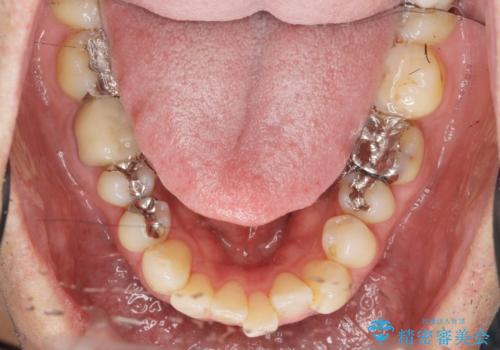

矯正と虫歯のセラミック治療 総合歯科治療の実践

- 突き出た前歯の角度の改善と虫歯治療の改善を求めて来院されました。

虫歯を除去したのち、マウスピース矯正治療を行い、歯並びやがたつきを改善したのち、セラミックに置き換えることで審美性の向上を計画します。